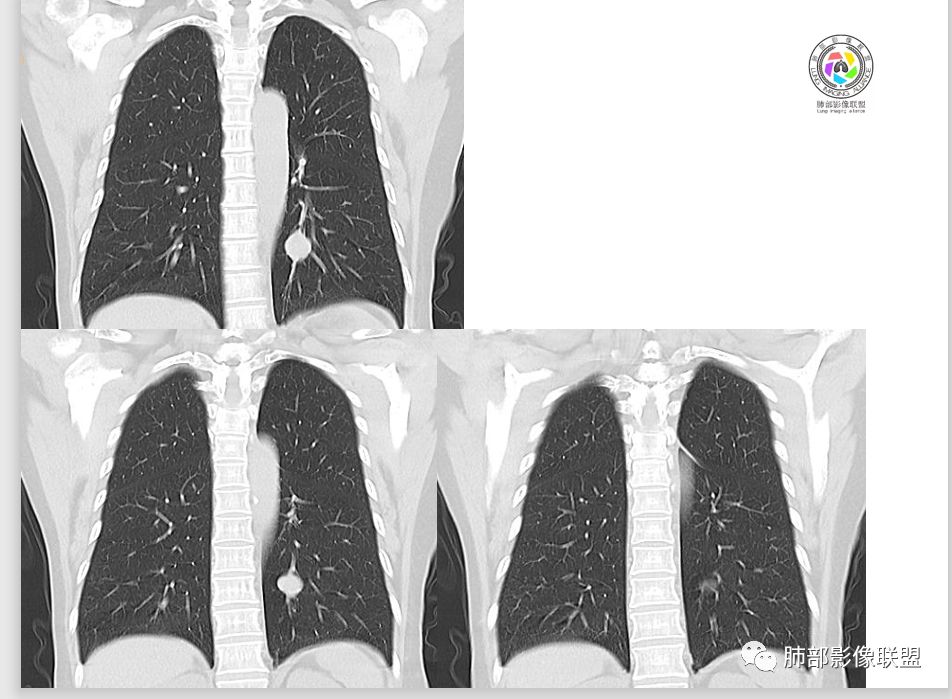

1.肺内如此大小的周边较光滑的孤立结节影或块影,密度较均匀的,一般会想到硬化性肺细胞瘤、错构瘤、小细胞癌、大细胞癌、类癌,以及单发转移灶等。

2.边缘光整,坏死不明显,未显示阻塞性炎症或不张,女性患者,肺鳞癌不支持。

3.缺乏典型深分叶及毛刺,强化不显著,似乎也缺乏肺腺癌的影像学特点。

4.未见脂质密度及钙化,强化程度等均不支持错构瘤。

5.同样病灶轻到中度强化也不支持类癌及大多数的硬化性肺细胞瘤(血管瘤样区为主)。

后者不能排除,毕竟不是所有的硬化性肺细胞瘤强化都那么显著。

6.转移瘤缺乏相关临床支持。

7.病灶的形态及强化程度都不能排除小细胞癌及大细胞癌,纵隔尤其是隆凸下未见增大淋巴结似乎不符合小细胞癌等的生物学行为。